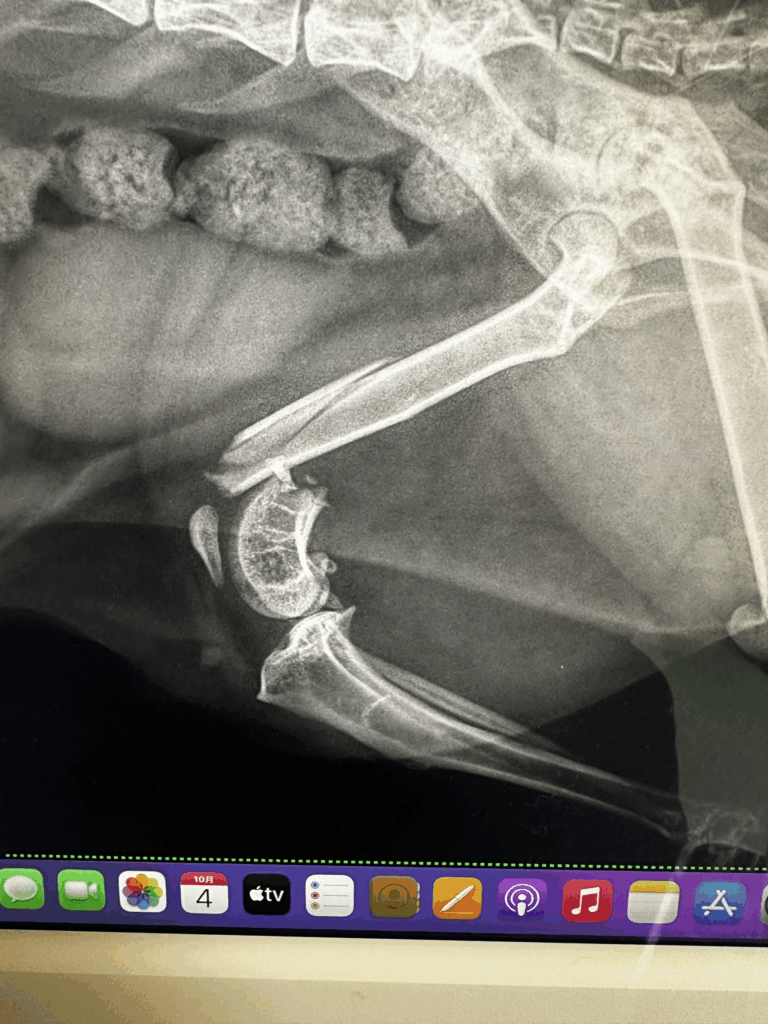

レントゲンで分かる骨折の現実

診察では触診に加え、必ずレントゲン検査を行います。大腿骨骨折にはさまざまなタイプがあり、

- 斜めに割れる「斜骨折」

- 粉々になる「粉砕骨折」

- 関節にまで及ぶ「関節内骨折」

といった形態が存在します。

特に猫の大腿骨骨折は プレートやピンなどの整形外科用のインプラントを使った手術 が必須となることが多く、ただ包帯やギプスで固定するだけではまず治りません。